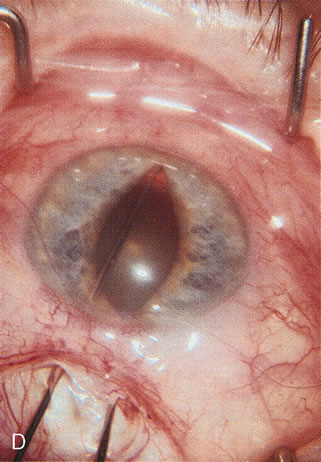

Fig. 1. The anatomic advantage of small incision cataract surgery for the glaucoma patient. A. Long-term bleb function with a large cataract incision is difficult to achieve with either ECCE-trabeculectomy or trabeculectomy followed later by ECCE. This bleb failed to form sufficiently when combined with large incision ECCE. The inflammation, bleeding, and long-term wound healing with stimulation of fibroblasts associated with this technique are more likely to cause bleb failure. In addition, the increased iris manipulation necessary to deliver the nucleus and subsequent iris repair adds to the long-term breakdown of the blood aqueous barrier. B and C. Two-site phacotrabeculectomy has the advantage of small incision cataract surgery combined with separate site trabeculectomy. The incision size is one third the size of the standard ECCE. The inflammation is less severe, and cataract wound healing is confined to the temporal area. Visual rehabilitation with phacoemulsification and foldable IOL is much faster. Phacoemulsification allows successful lens extraction even in the unfriendly environment of a smaller pupil compared with ECCE. The trabeculectomy is performed in an entirely different site, well away from the wound healing associated with temporal phacoemulsification. The likelihood of this filter functioning long-term is greater than with ECCE-trabeculectomy. D. The surgeon also has the option of single-site phacotrabeculectomy with foldable IOL. Both the lens extraction and trabeculectomy are performed through one small 3.5-mm limbal incision.

Fig. 3. Partial bleb failure following clear corneal phacoemulsification with foldable IOL. A. Preoperative bleb appearance prior to temporal lens extraction. Preoperative IOP was 12 mm Hg on no antiglaucoma medications. Time from 5-FU trabeculectomy surgery to lens extraction was one year. B. Bleb appearance 2 months after clear corneal cataract surgery with topical anesthesia. Following lens extraction, increased vascularity was noted along with decreased size of the filtering bleb. IOP increased to 20 mm Hg as early as 2 weeks after surgery, necessitating topical antiglaucoma therapy. C. High magnification view of bleb before lens extraction demonstrates diffuse pale bleb. D. High magnification view of bleb 2 months after surgery. There are vessels surrounding the nasal side of the bleb and the overall bleb size is smaller.